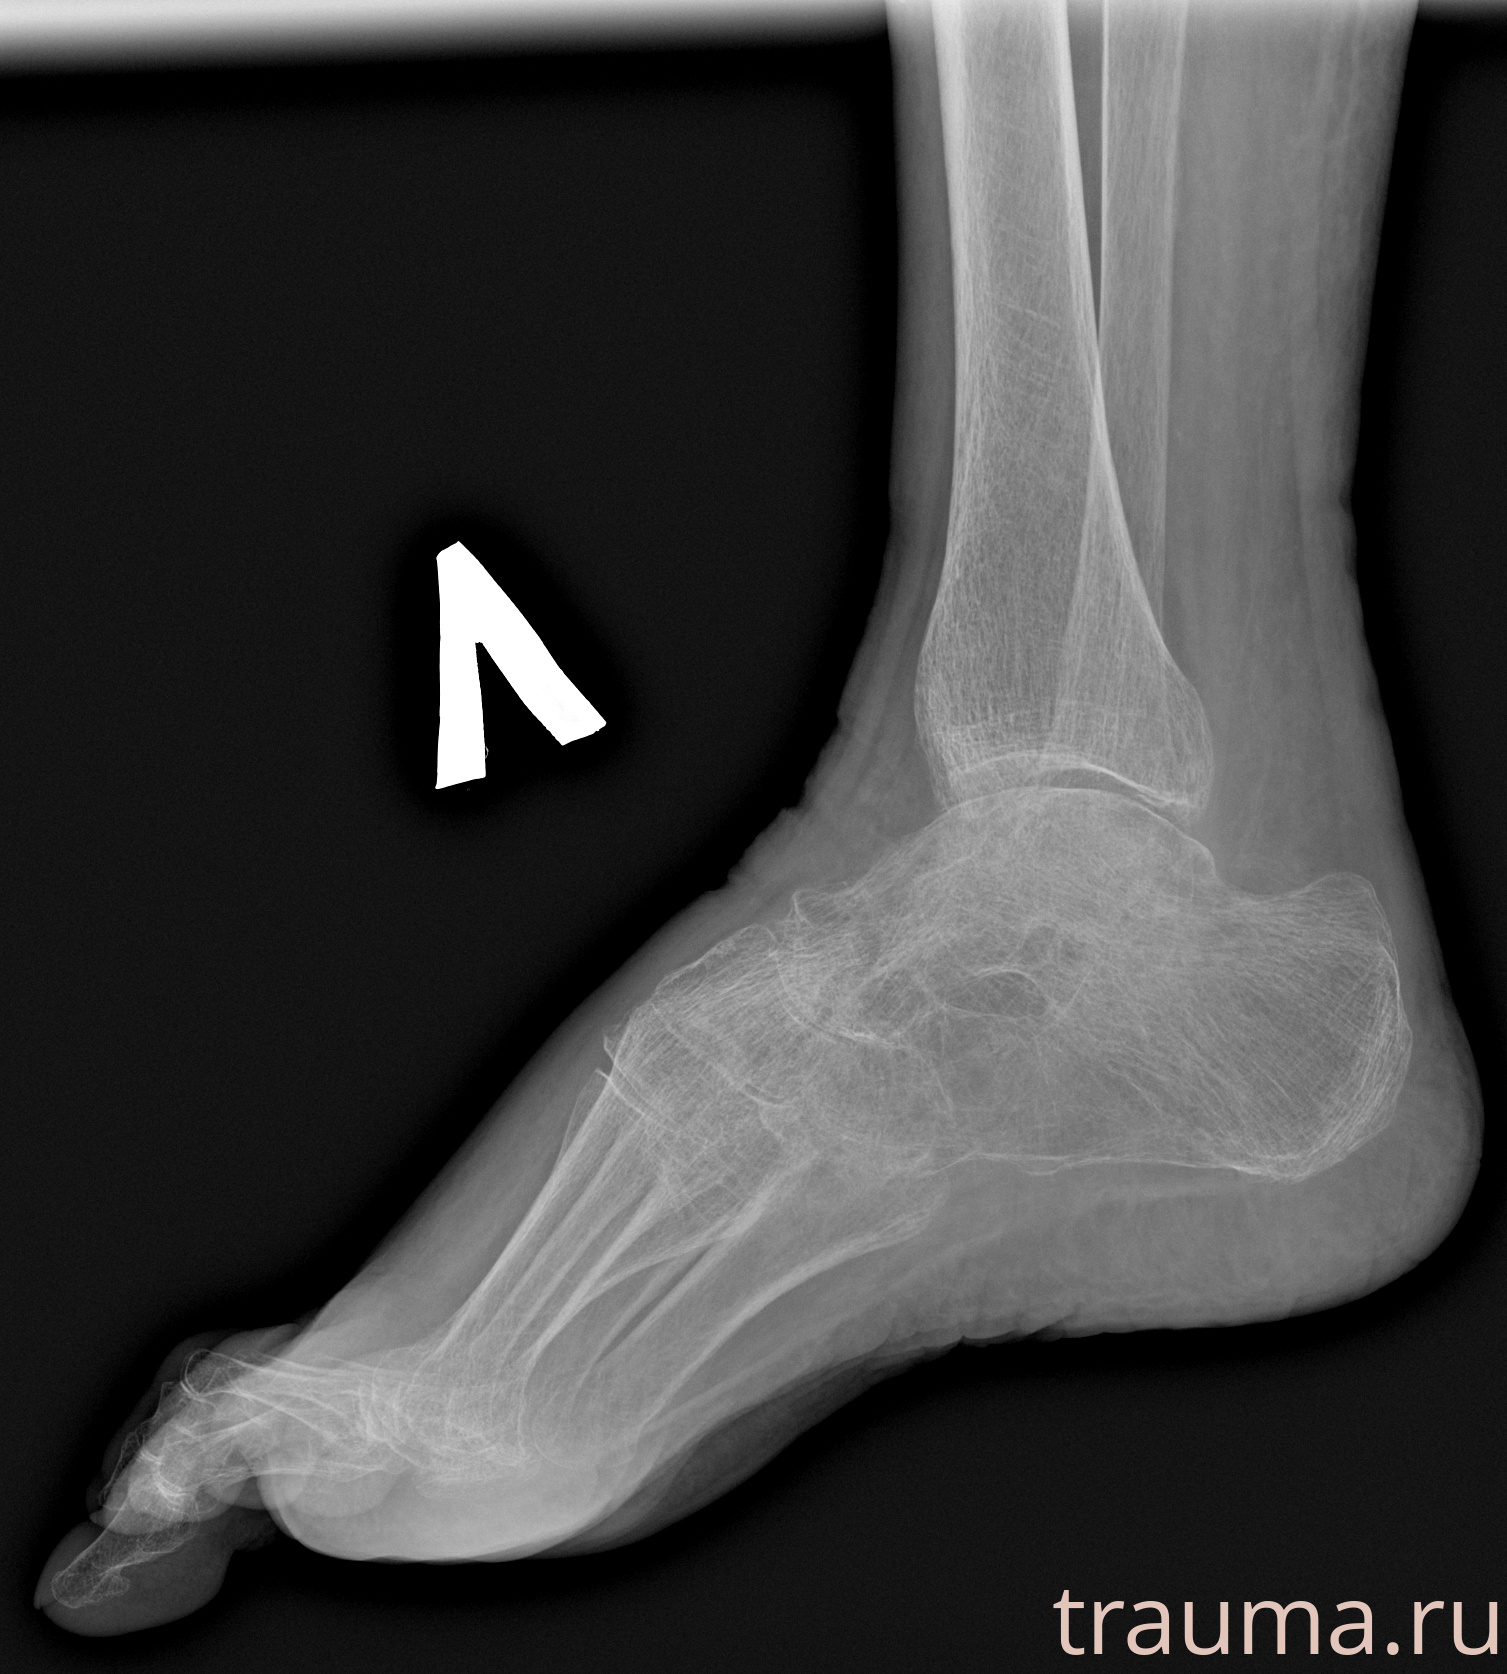

Рентген на дому: по вашему адресу приезжает врач-рентгенолог, травматолог-ортопед с мобильным рентгеновским аппаратом, проводит диагностику травмы или заболевания, делает необходимые рентгенограммы, дает рекомендации по дальнейшему лечению. Получить качественные снимки в домашних условиях возможно благодаря уникальной методике, разработанной МосРентген Центром для института  Склифосовского